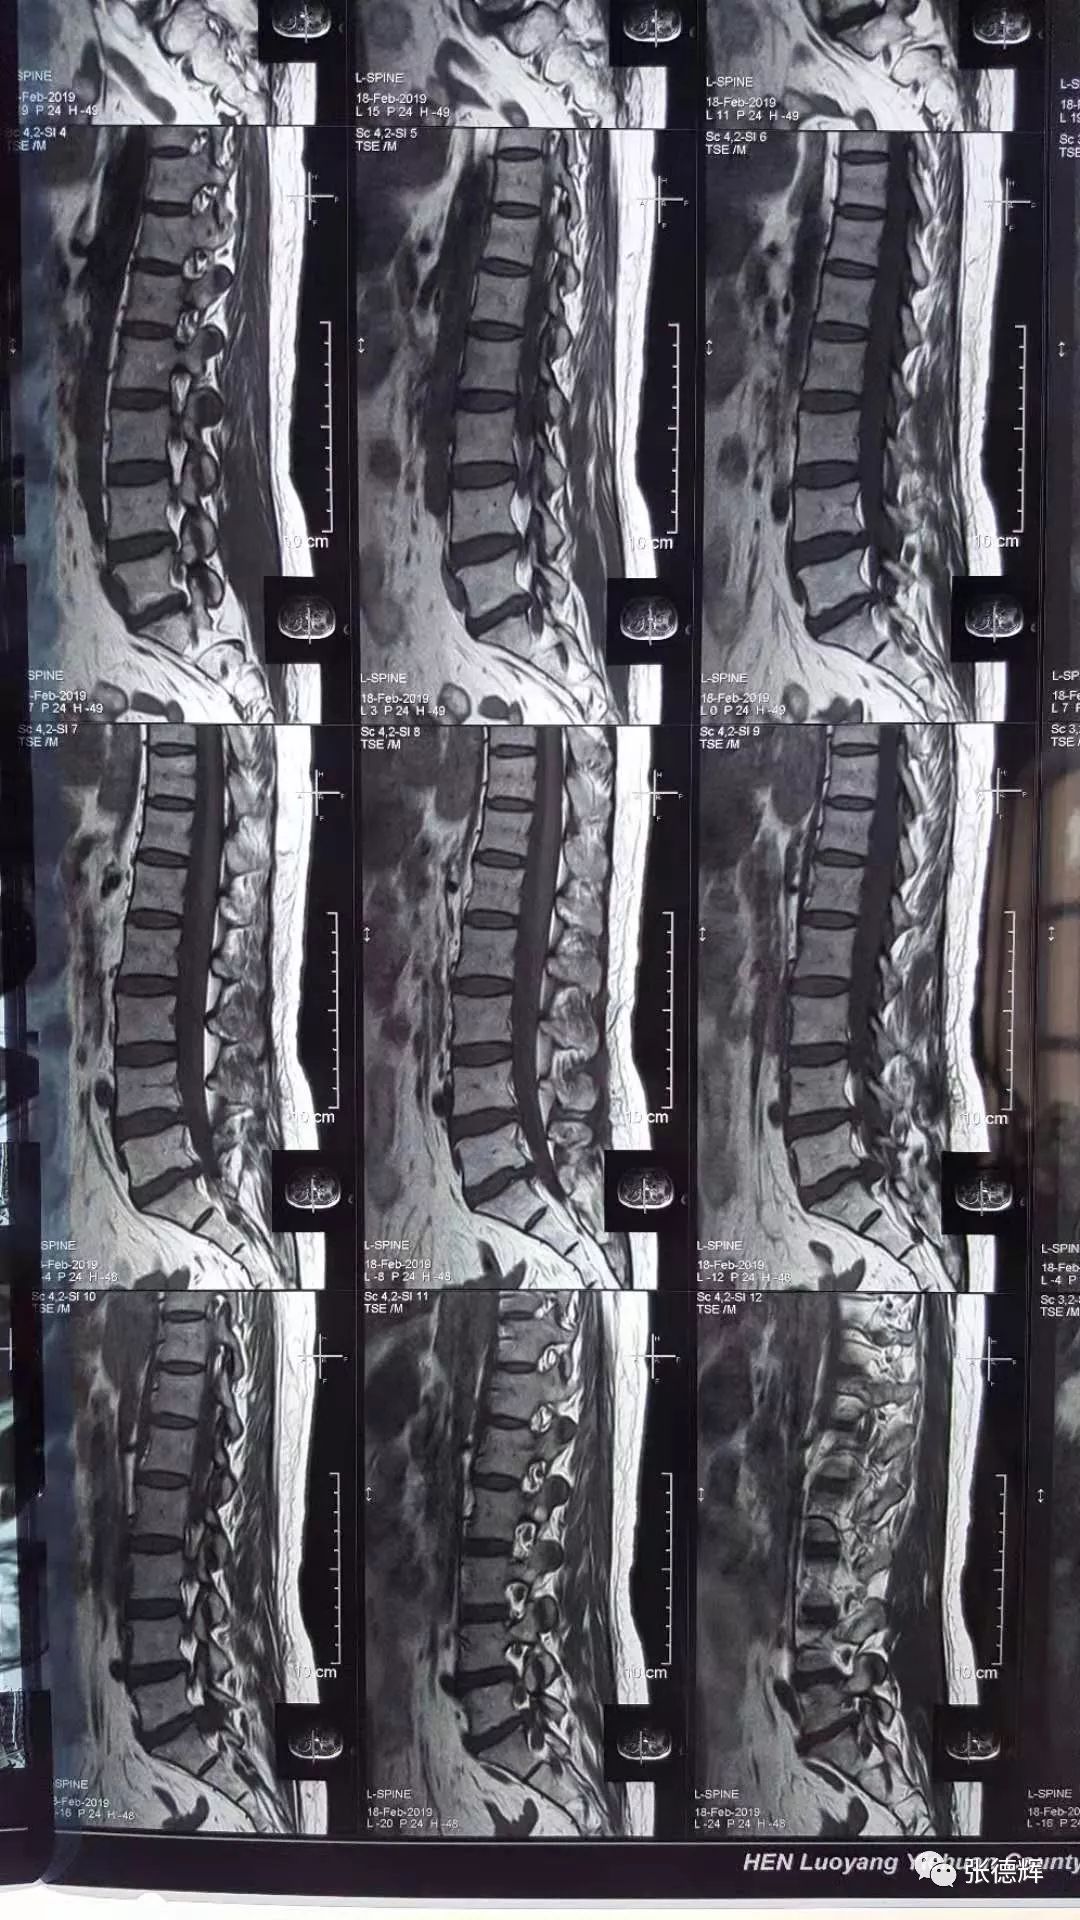

患者术前的各项影像检查

腰椎核磁及CT均提示腰5-骶1巨大椎间盘脱出,椎管占位,马尾神经受压明显

根据患者的这些临床症状及其影像学检查结果

我们判断—— 患者为“ 腰5骶1巨大椎间盘脱出 ”并有“ 马尾综合征 ”迹象